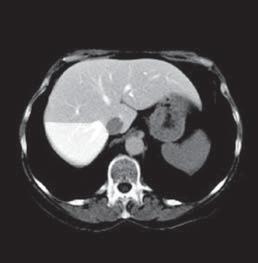

Kazuistika I (segmenty jaterní tkáně)